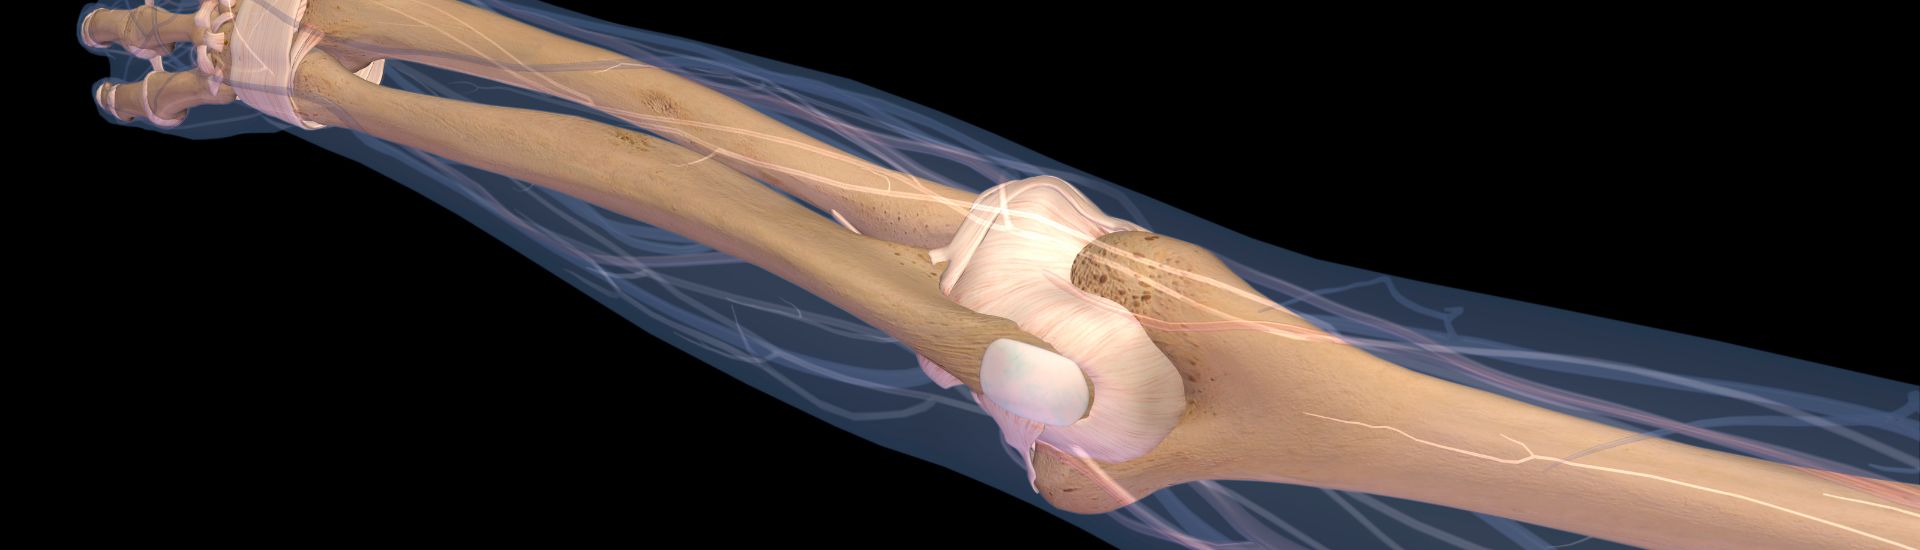

L’RX Gomito, conosciuto anche come radiografia del gomito, è un esame radiologico che utilizza i raggi X per ottenere immagini dettagliate delle ossa del gomito. Questa procedura permette ai medici di individuare lesioni, fratture e altre anomalie, fornendo una visione completa dell’articolazione. Al Poliambulatorio S-Medical Group di Sora, ci avvaliamo di tecnologie avanzate e specialisti esperti per offrire un servizio diagnostico di altissima precisione.

Grazie a un RX Gomito è possibile visualizzare chiaramente le strutture ossee che compongono l’articolazione, tra cui ulna, radio e omero. Questo esame permette di identificare con precisione: